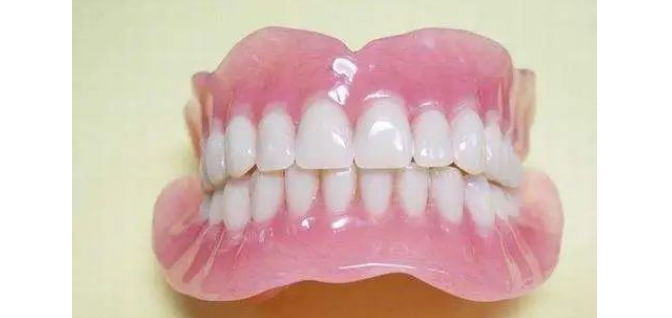

图2:全口义齿(活动假牙)

很多朋友会抱怨说,活动假牙戴一段时间后,会变得越来越松了。

说话、咀嚼、微笑和打喷嚏时,会出现移动、翘动甚至脱落。

这其中有两个原因:

一是,活动假牙大多是直接安装在牙床上,咀嚼食物时,咬合力就会直接压迫牙槽骨。

时间长了就会出现牙槽骨吸收,最终导致牙槽骨萎缩,原本较为紧的假牙就会出现松动。

二是,制作活动假牙的材料主要是塑胶类。常用的是复合树脂,不耐磨。

假牙磨损后,有压痛、咬合异常等问题,应及时进行修补或更换。

活动假牙一般有卡环。卡环扣在邻牙上作为支撑,这样稳定性坚固性也会较好。

但是每天取几次,对邻牙会造成一定的危害。

并且邻牙上的卡环也不好清洁,容易堆积菌斑。邻牙也更容易出现龋坏。

长期佩戴活动假牙,假牙长时间磨耗边缘会变得锐利,这很容易造成口腔黏膜创伤,出现口腔溃疡,影响口腔健康。